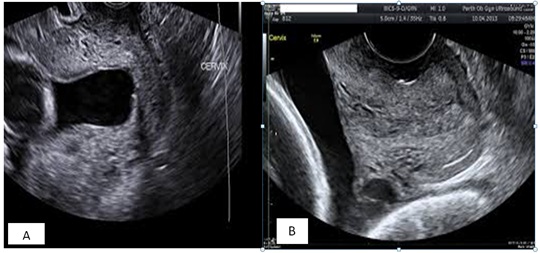

The risk of cervical dilatation and ascending infection is higher when CL <15 mm [5]. Women with extreme short CL <10 mm have been shown to benefit more from cerclage than vaginal progesterone alone; (Figure 2). Some patients develop progressively worsening short cervix <10 mm despite being on daily vaginal progesterone, or are diagnosed at first CL assessment with TVUS with short cervix, CL <10 mm. Unfortunately, vaginal progesterone has been found to be less effective in this category of patients. Hence, cervical cerclage is recommended in women with extreme short cervix <10 mm. In an Individual Patient Data (IPD) meta-analysis and systematic review by Berghella et al., in 2017, cervical cerclage was significantly more effective (39.5% versus 58.0%) than vaginal progesterone in patients with CL <10 mm (RR 0.68, 95% CI 0.47 - 0.98) [13]. Similarly, Enakpene et al., in their study of singleton pregnant women with short cervix on vaginal progesterone who develop progressively shortening CL <10 mm, cerclage in combination with vaginal progesterone compared to vaginal progesterone alone was more effective in the reduction of sPTB (RR 0.52, 95% CI 0.35 - 0.78, p = 0.001). Pregnancy was also more prolonged in the combined group; 14 weeks versus 7 weeks with associated reduction of overall adverse perinatal outcomes [19]. The positive outcomes of this study make serial CL surveillance in patients on vaginal progesterone for incidental short cervix a practice to be considered so that appropriate intervention can be promptly instituted. Individual institution should be discretional in adopting this practice because it will increase the number of clinic visits, workload for the healthcare staff as well as economic burden. However, the beneficial effect of prevention of one single preterm birth may quite outweigh the burden of having extremely premature babies in the neonatal intensive care unit, and its accompanied complications and sequelae.

Figure 2: Pre-cerclage (A) and post-cerclage (B) cervical images of patient with CL <10 mm.

Ultrasound images of the cervix before cerclage, and two weeks after cerclage placement.